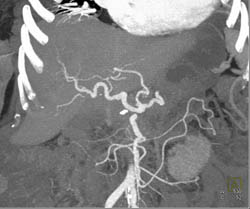

Islet Cell Tumor With Cavernous Transformation of the Portal Vein (CTPV) and Splenic Vein Occlusion